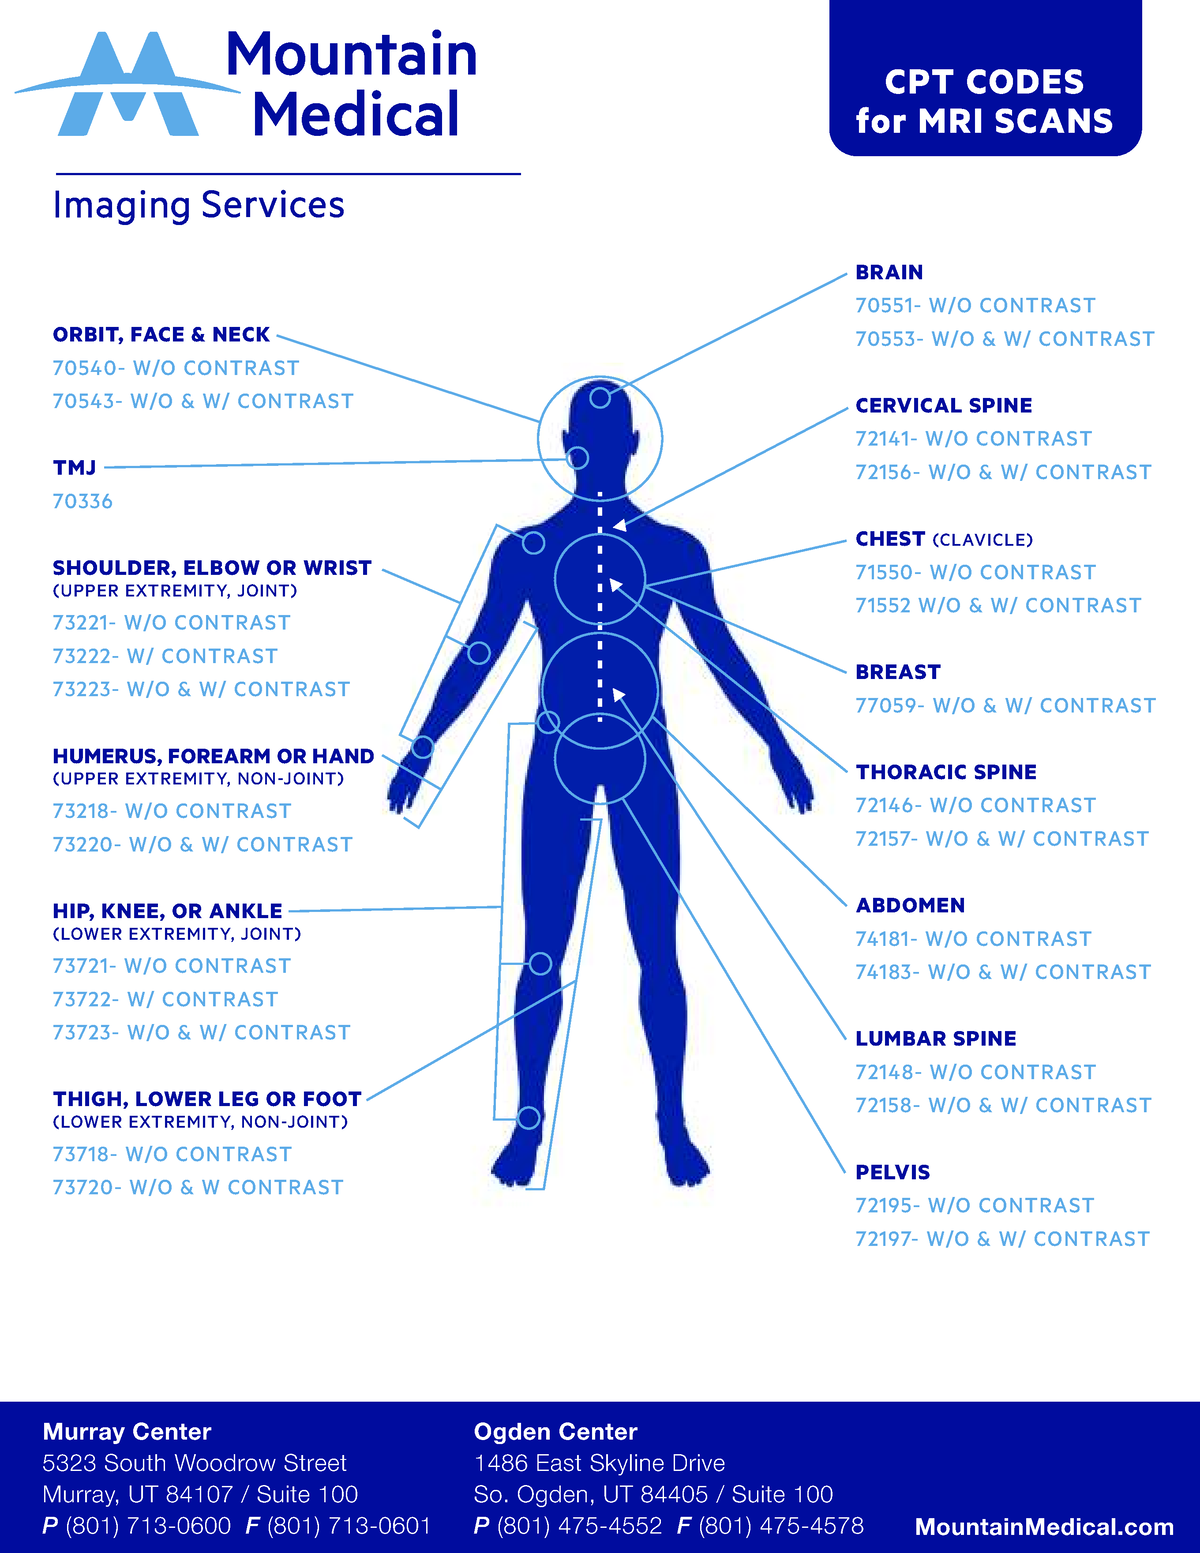

2025 Cpt Codes List Rosie C Pearce

Mri Knee Cpt Code 2024 Alyson Andreana